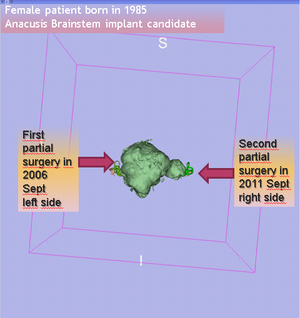

- 5.26 Imaging in Audiology: A Case Report of a Patient with Bilateral Acoustic Neuroma